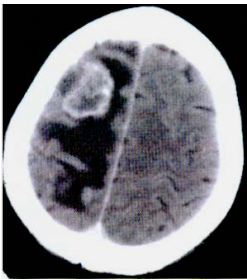

52 65 歲女性,十天來逐漸發生左側肢體無力,講話困難。根據此注射含碘顯影劑 CT 影像,最可能的 診斷是:

(A) Acute infarction with hemorrhage(hemorrhagic infarction) (B)Acute infarction with gyral pattern enhancement (C)Metastasis (D)High grade astrocytoma